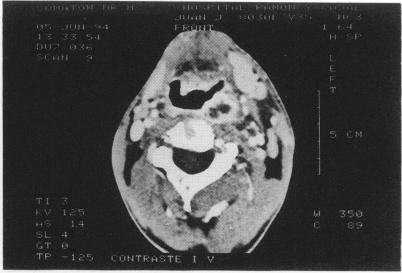

Dysphagia in a diabetic patient.

Department of Endocrinology, Ramon y Cajal Hospital, Madrid, Spain.

Postgrad Med J. 1995 Nov;71(841):683-4. doi: 10.1136/pgmj.71.841.683.

https://cdn.ncbi.nlm.nih.gov/pmc/blobs/8748/2398342/5266e02032db/postmedj00035-0045-b.jpg